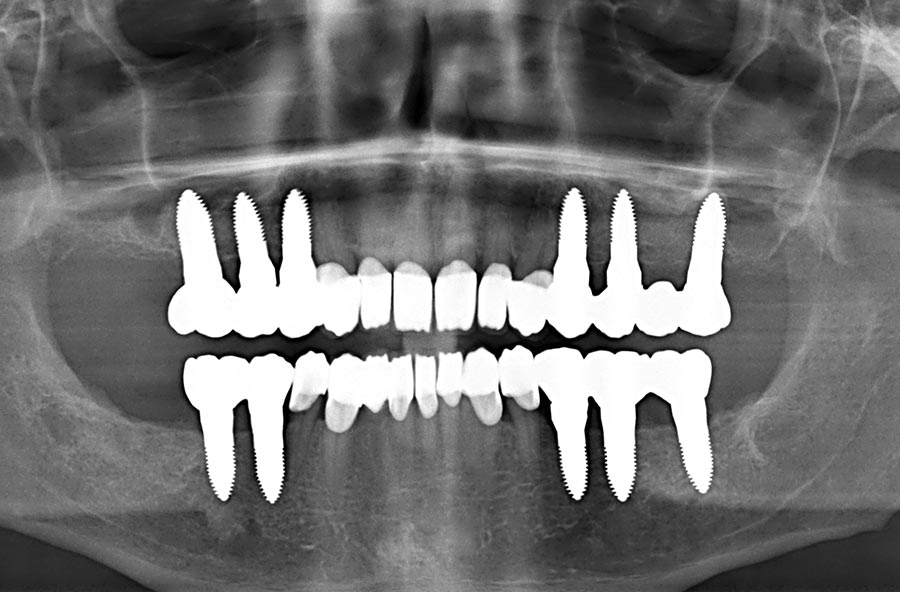

der obige Fall röntgenologisch vorher

Vorher: der obige Fall röntgenologisch vorher

man kann die Keramik-Implantate und den erfolgreichen Knochenaufbau im Unterkiefer, aber auch in beiden Kieferhöhlen (offener Sinuslift) sehr gut erkennen; auch den perfekten Sitz aller vollkeramischen Kronen

Nachher: man kann die Keramik-Implantate und den erfolgreichen Knochenaufbau im Unterkiefer, aber auch in beiden Kieferhöhlen (offener Sinuslift) sehr gut erkennen; auch den perfekten Sitz aller vollkeramischen Kronen